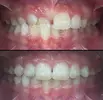

Crooked Teeth